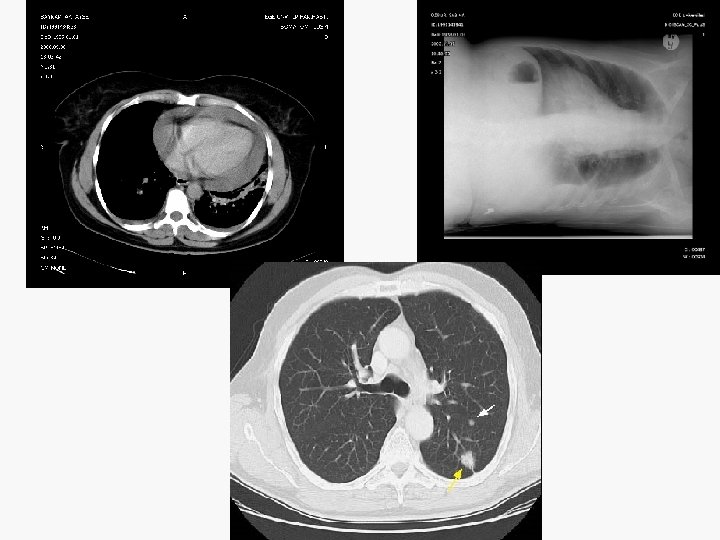

Evreleme EVRE 0 : Tis N 0 M 0 EVRE IA : T 1 N 0 M 0 EVRE IB : T 2 N 0 M 0 EVRE IIA : T 1 N 1 M 0 EVRE IIB : T 2 N 1 M 0 T 3 N 0 M 0 EVRE IIIA : T 1 -3 N 2 M 0 T 3 N 1 M 0 EVRE IIIB : T 4 N M 0 T N 3 M 0 EVRE IV : T N M 1

Non-invaziv evreleme (1) Toraks BT’de kısa çapı 1 cm’den büyük LAM’lar anlamlı kabul edilir ama bu metastatik anlamına gelmez. Toraks MR – Süperior sulkus tümörlerinin evrelemesinde kullanılmalı – Mediasten ya da toraks duvarı invaz. değerlendirmek için önerilmez.

Non-invaziv evreleme (2) Metastaz kuşkusunu arttıran bulgular her hastada sorgulanmalıdır. – – – – – Kilo kaybı (>%10) Lokal kemik ağrısı, kemiklerde hassasiyet Nörolojik semptomlar ya da bulgular >1 cm periferik LAM Ses kısıklığı, VCSS Hepatomegali Yumuşak doku kitlesi Anemi (erkekte <%40, kadında <%35) Ca, ALP, SGOT, GGT yüksekliği